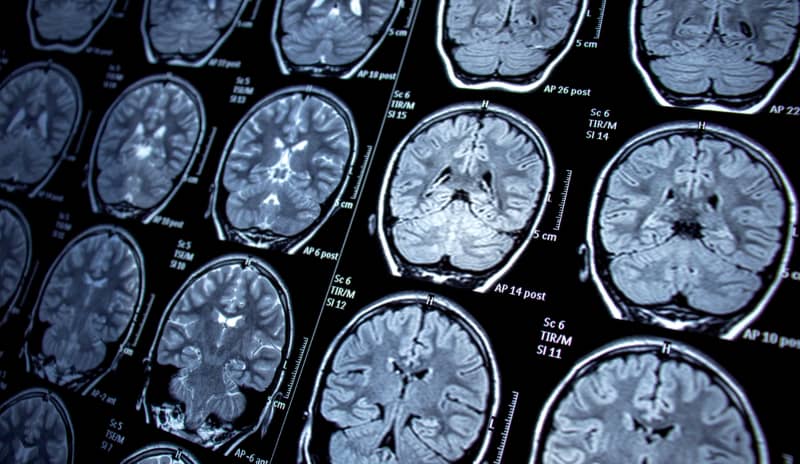

Pie de foto

tipos de epilepsia

• Resonancia magnética (RM): imágenes extremadamente detalladas del cerebro, proveen más información que un TAC.